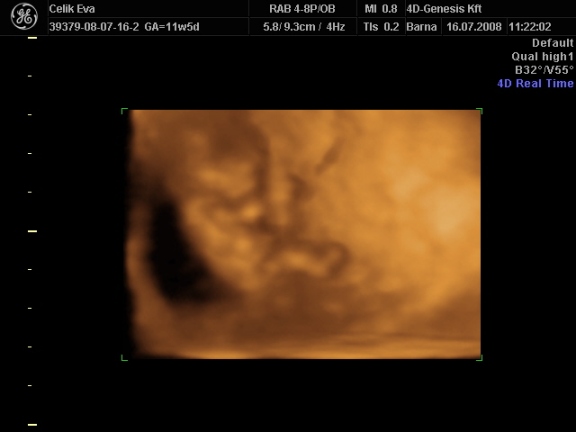

3d-s babafotók:

Kép

ha megfürödtek a fiuk rakok fel 2d-s fütyis képeket is,meg egyet amin olyan édes arcocskája van :lol: